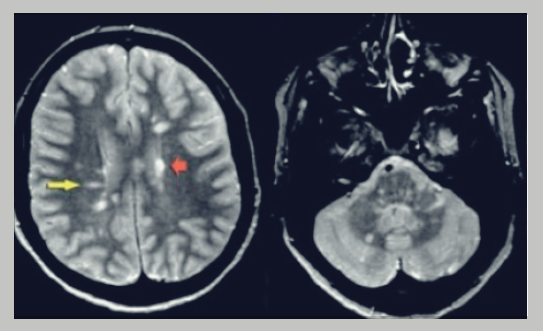

이 질병은 장기간에 걸쳐 뇌와 중추 신경계의 다른 구성 요소를 천천히 악화시키는 퇴행성 특성을 나타낸다. 안타깝게도 이 질병은 호전되어도 다시 재발하는 패턴을 자주 보여준다. 회복 단계로 보이는 동안에도 신경계의 미란, 특히 뇌와 척수의 신경 섬유 주변을 보호하는 미엘린(myelin)이 파괴된다. 이 과정의 영향을 받는 개인은 전반적인 건강과 기능에 좋지 않은 결과를 초래하기도 한다.

일반적으로 뇌와 척수를 포함한 중추 신경계의 여러 부분을 번갈아 침범하면 재발할 수도 있다. 이렇게 침범하면 기존 증상을 악화시키거나 새로운 증상의 유발을 야기시킨다. 이 주기적인 패턴은 신경계의 점진적인 손상 축적에 기여해 궁극적으로 시간이 지남에 따라 심각한 장애로 이어지게 된다. 질병의 재발 특성은 환자에게 중요한 문제이기에 지속적인 관리와 치료 방법이 필요할 것이다.